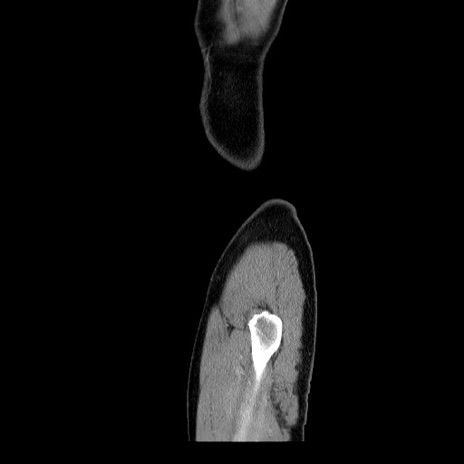

横断像